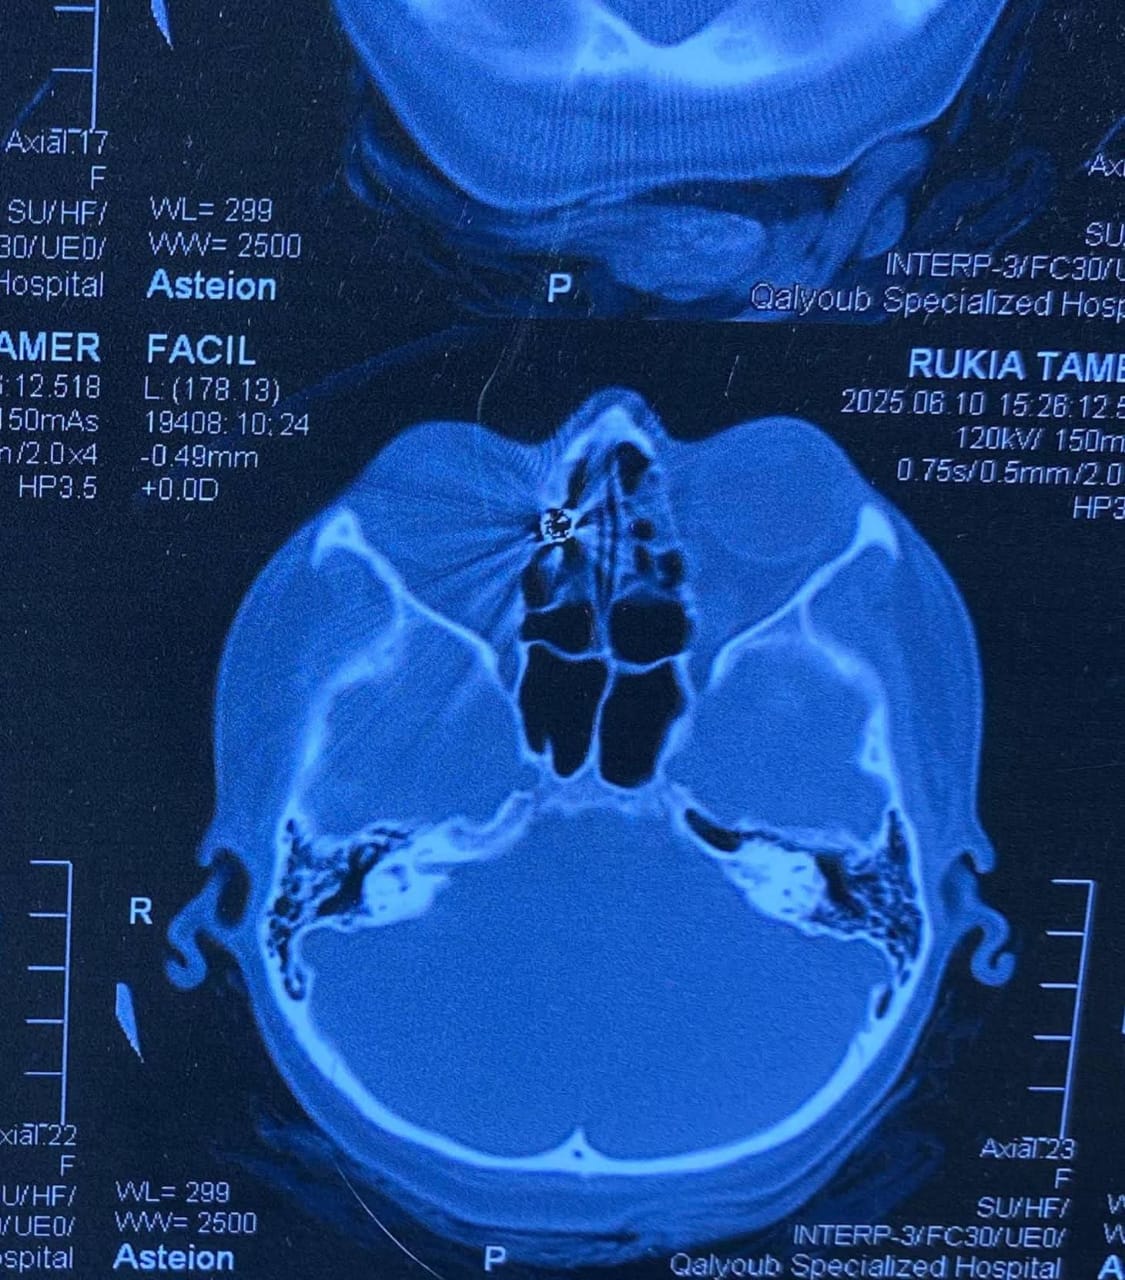

وكانت المريضة قد حضرت إلى المستشفى تعاني من نزيف بالأنف وتورم بالعين، عقب ادعائها الإصابة بطلق ناري من بندقية صيد، وعلى الفور، تم إجراء أشعة مقطعية على الأنف والجيوب الأنفية، والتي أظهرت وجود جسم غريب معدني مستقر داخل الجيوب الأنفية الغربالية.

وعلى إثر ذلك، تم التعامل مع الحالة بشكل عاجل، حيث جرى إدخالها إلى عمليات قسم الأنف والأذن والحنجرة، وتمكن الدكتور علاء عبدالسميع، أستاذ مساعد الأنف والأذن والحنجرة، بمشاركة الفريق الطبي المعاون من أطباء وتمريض العمليات، من استخراج الطلقة بنجاح باستخدام منظار الجيوب الأنفية، دون حدوث أي مضاعفات.